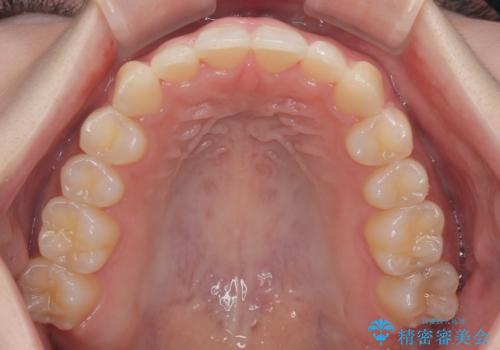

前歯が隠れるほどのデコボコをインビザライン矯正できれいに整える

- 前歯のデコボコを気にして来院された患者様です。

全体的にデコボコが多く、特に下の前歯は隠れてしまうほどの状態でした。

左右ともに奥歯の咬み合わせが理想的な位置にあったこともあり、患者様のご希望通り、インビザラインにて矯正治療を行うこととしました。

マウスピース矯正特有の、奥歯が噛みにくくなるという現象の解消に少し期間をいただきましたが、日々の装着時間を遵守していただき、綺麗な歯列に整えることができました。